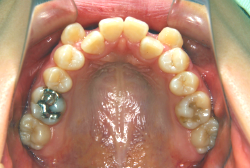

「歯並びの凸凹を直したい」という主訴で来院したケースです。診断の結果、たしかに「叢生」という隙間が足りないと言うことが原因の凸凹症例でした。

しかし、それ以上に問題なのは「前歯の噛み合い方が深すぎる」という症状で、初診の歯の正面写真を見ると下の前歯が全く見えません。こういう症状を矯正学では「過蓋咬合(かがいこうごう)」と言います。過蓋咬合を放置すると、将来的に顎関節に悪影響を与えるとされており、顎関節症の原因因子の一つです。また下の前歯の先端が、上の前歯の裏側の歯茎と強く接触するため、歯周病の原因にもなります。

検査の結果、凸凹が軽症なため非抜歯で矯正すること可能と判断、マルチブラケット装置にて治療しました。治療後は歯並びが綺麗になっただけでなく、噛み合わせ的にも正しい状態が確立しています。